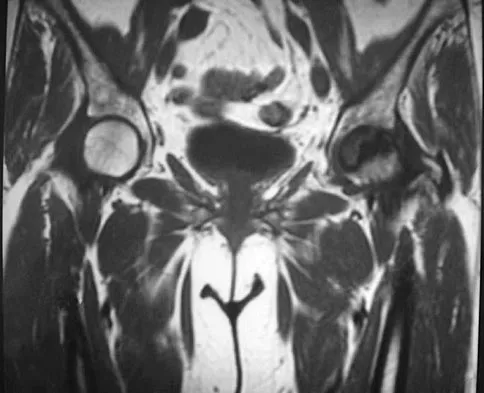

Question 61

Figures 28a through 28c show the MRI scans of a 30-year-old woman who weighs 290 lb and has low back and left leg pain. She also reports frequent urinary dribbling, which her gynecologist has advised her may be related to obesity. Examination will most likely reveal

Explanation